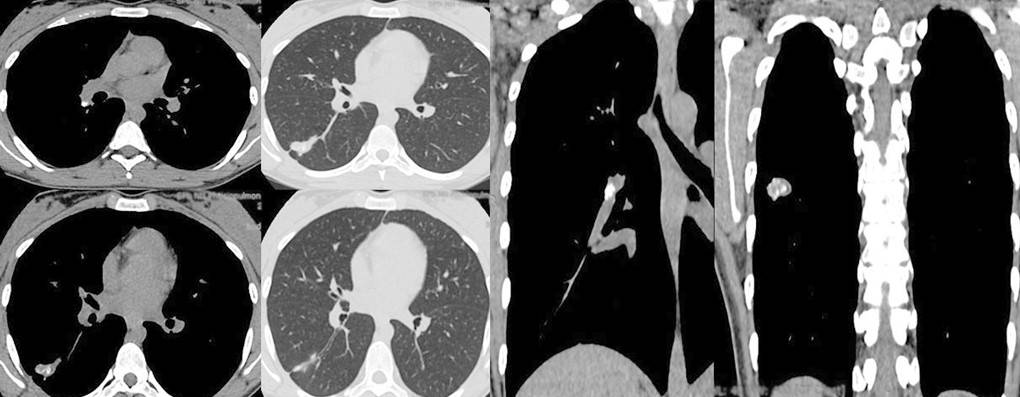

В 2020 году была разработана эмпирическая шкала визуальной оценки легких, в которой КТ-0, КТ-1, КТ-2, КТ-3 и КТ-4 соответствуют стадии заболевания и, соответственно, степени поражения легких.

Врач изучает каждую долю легкого (всего 5) на посрезовых сканах в поперечной и фронтальных плоскостях и оценивает объем поражения каждой по пятибалльной шкале. Если признаки воспаления отсутствуют, рентгенолог присваивает значение 0 и так далее. Если воспалительные очаги и инфильтраты присутствуют в нескольких сегментах, такую пневмонию называют полисегментарной. При коронавирусе пациентам чаще всего диагностируют двустороннюю полисегментарную пневмонию. При своевременном обращении за медицинской помощью распространение инфекции в легких можно остановить.

Степени поражения легких при коронавирусе на КТ

В заключении КТ легких пациенты видят аббревиатуры: КТ-0, КТ-1, КТ-2, КТ-3 и КТ-4 Что они обозначают?

- КТ-0 —очаги воспаления и инфильтраты не выявлены, легкие «чистые»;

- КТ-1 —поражение легких до 25%;

- КТ-2 —поражение легких 25-50%;

- КТ-3 —поражение легких 50-75%;

- КТ-4 —поражение легких > 75%.

По данным исследования «Time Course of Lung Changes at Chest CT during Recovery from Coronavirus Disease 2019 (COVID-19)», опубликованного в июле 2020 года в международном журнале Radiology, максимальное поражение легких (пик пневмонии) у большинства пациентов наблюдается на 10 день заболевания. В выборку не вошли пациенты со специфическими осложнениями, такими как ОРДС, кардиогенный отек легкого, тромбоз, тяжелые последствия которых носят непредсказуемый характер.

Как коронавирус выглядит на КТ?

При коронавирусе на КТ отчетливо и ясно визуализируются инфильтраты в легких — участки, заполненные экссудатом (жидкостью, кровью, гноем), вследствие чего дыхание затруднено.

По данным актуальных исследований, публикуемых в журнале Radiology, вирусная пневмония, вызванная COVID-19, чаще всего проявляется на КТ изображениях в виде двухсторонних затемнений по типу «матового стекла» и уплотнений легочной ткани, например, утолщения альвеолярных перегородок. На томограммах это, напротив, более светлые участки, поскольку они свидетельствуют о повышенной плотности легочной ткани, а она хуже пропускает рентгеновские лучи.

Наличие одиночного очага поражения по типу «матового стекла» в правой нижней доле легкого может быть интерпретировано как начальное, самое первое проявление вирусной пневмонии.

Отметим, что «матовые стекла» не являются специфическим признаком пневмонии при коронавирусе. Этот признак характерен для опухолей, кровоизлияний и других инфекций. По результатам КТ легких возможна лишь первичная дифференциальная диагностика пневмоний (бактериальной, вызванной пневмококком, грибками и др.). «Рисунок» этих заболеваний может лишь незначительно различаться. Чтобы врачи могли правильно поставить диагноз, пациенту следует пройти дополнительное обследование, например, сделать ПЦР. Лабораторная диагностика поможет выявить специфического возбудителя воспаления легких.

Когда заболевание переходит в более позднюю стадию, рисунок становится более специфическим. Коронавирусную пневмонию на КТ легких определяют по следующим признакам.